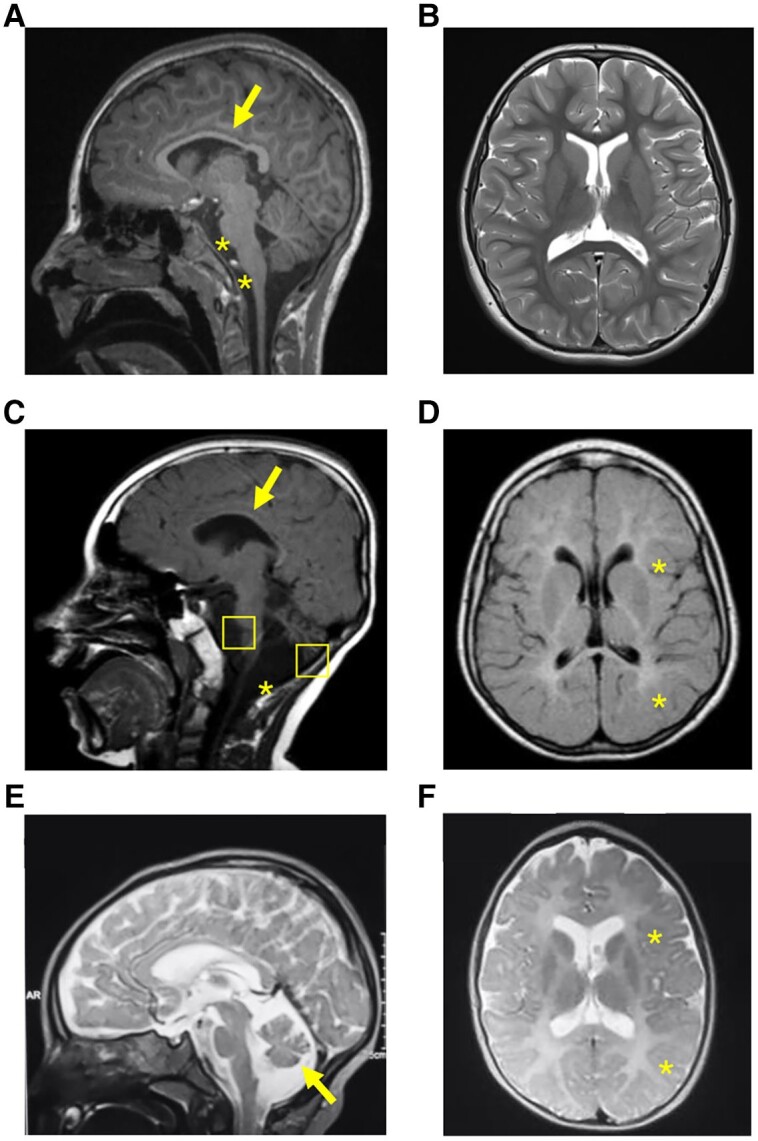

Figure 3

MRI sections of the brain of the three probands harbouring biallelic PTMT1 variants. (A) T1 sequence, sagittal view. Evidence of thin corpus callosum (arrow), atrophy of pons and medulla (star). (B) T2 sequence, axial view. No white or grey matter changes were observed. (C) T1 sequence, sagittal view, showing hypoplasia of corpus callosum (arrow), cerebellar and brainstem atrophy (squares), and mega cisterna magna anomaly (asterisk). (D) T1 sequence, axial view, showing supratentorial white matter signal hyperintensity in keeping with hypomyelination. (E) T2 sequence, sagittal view, showing diffuse cortical atrophy, and cerebellar atrophy (arrow). (F) T2 sequence, axial view, showing areas of hypomyelination.